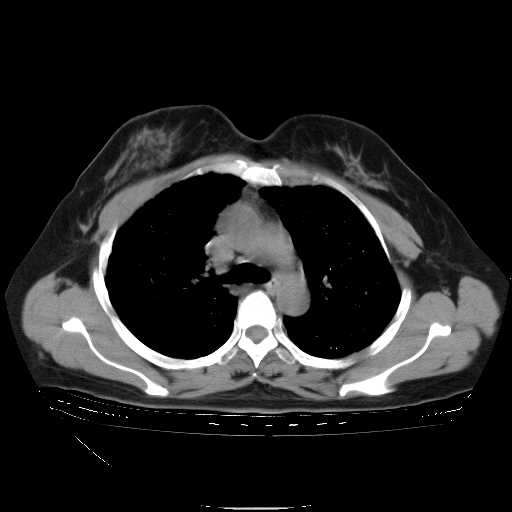

f50,肺ca治疗后,做过穿刺,确诊是肺ca,大家看看这是去年12月做的

下面是今天刚刚做的,在上海治疗,吃了家属也说不清的一种药,一个月1万左右,

考虑  腺癌肺内转移,治疗较前病灶缩小、减少

肺癌并肺内转移,这种疾病治疗后在影像上看略有好转,不是很显著,但是肿瘤治疗效果影像只是一方面。

支持肺癌并肺内淋巴管炎,  原发灶小了,但转移较前片明显了.

支持右肺下叶周围型肺癌并肺内淋巴管炎,  原发灶小了,但转移较前片明显了.。

标准的细支气管肺泡癌呀!治疗后病情有所控制,也没治愈的迹象!

支持右肺下叶周围型肺癌并肺内淋巴管炎;病灶有所控制。